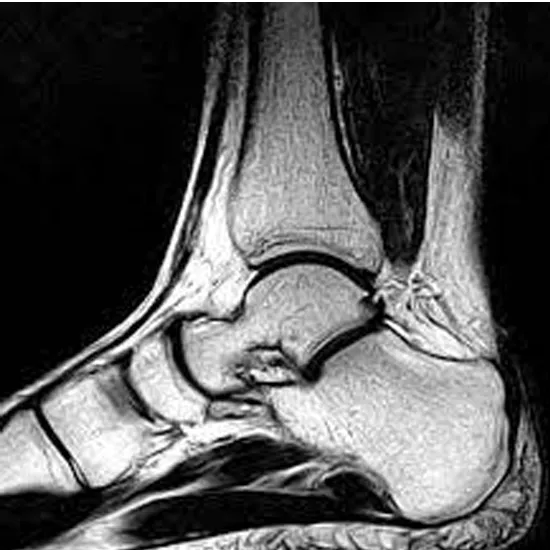

An MRI of both ankles with contrast is utilized to visualize the bones of the ankle joint (tibia and fibula) and the surrounding soft tissues, including tendons, ligaments, muscles, and blood vessels. Therefore, the contrast enhances the MRI scan's sensitivity and diagnostic accuracy by improving the internal organs' visibility.

MRI pictures give surgeons a road map for making repairs to broken bones, torn ligaments, and ruptured tendons. The physician prescribes this test to diagnose any fractured bones in the ankle joint.